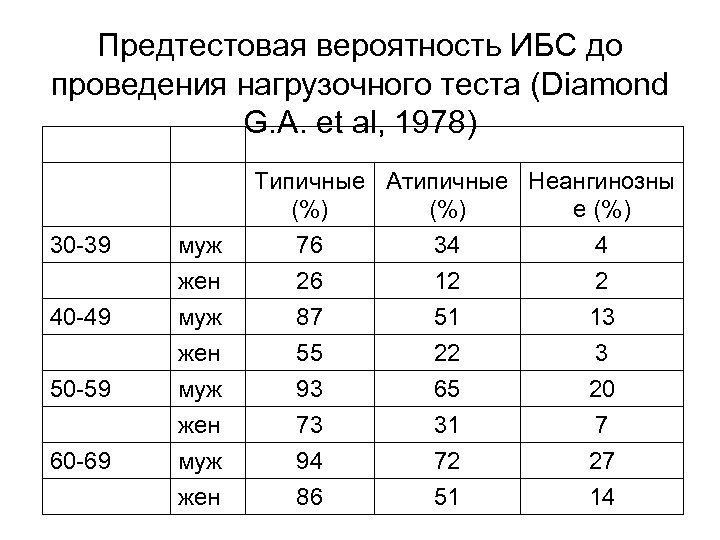

Предтестовая вероятность ИБС до проведения нагрузочного теста (Diamond G. A. et al, 1978) Возраст Пол Характер болей Типичные Атипичные Неангинозны (%) е (%) 30 -39 40 -49 50 -59 60 -69 муж жен 76 26 87 55 93 73 94 86 34 12 51 22 65 31 72 51 4 2 13 3 20 7 27 14

Предтестовая вероятность ИБС до проведения нагрузочного теста (Diamond G. A. et al, 1978) Возраст Пол Характер болей Типичные Атипичные Неангинозны (%) е (%) 30 -39 40 -49 50 -59 60 -69 муж жен 76 26 87 55 93 73 94 86 34 12 51 22 65 31 72 51 4 2 13 3 20 7 27 14